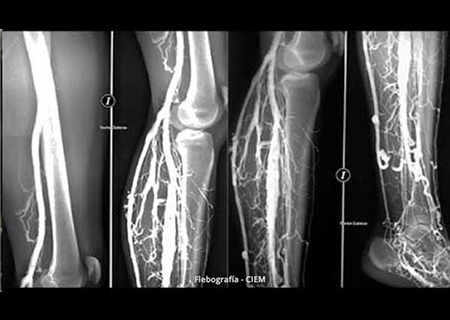

Flebografía

La venografía consiste en una exploración diagnóstica invasiva que permite el estudio de la circulación venosa de las extremidades inferiores. Las venas no son visibles en las radiografías simples. Para poder visualizarlas mediante un estudio de rayos X es necesario la inyección de un contraste venoso. El contraste es una sustancia radiopaca que no permite el paso de los rayos X a través de su superficie, por lo que permite visualizar aquellas venas que lo contienen. Durante la práctica de la prueba pueden tomarse varias radiografías para visualizar el llenado progresivo de los vasos y detectar estrechamientos, obstrucciones o la presencia de vasos anómalos.